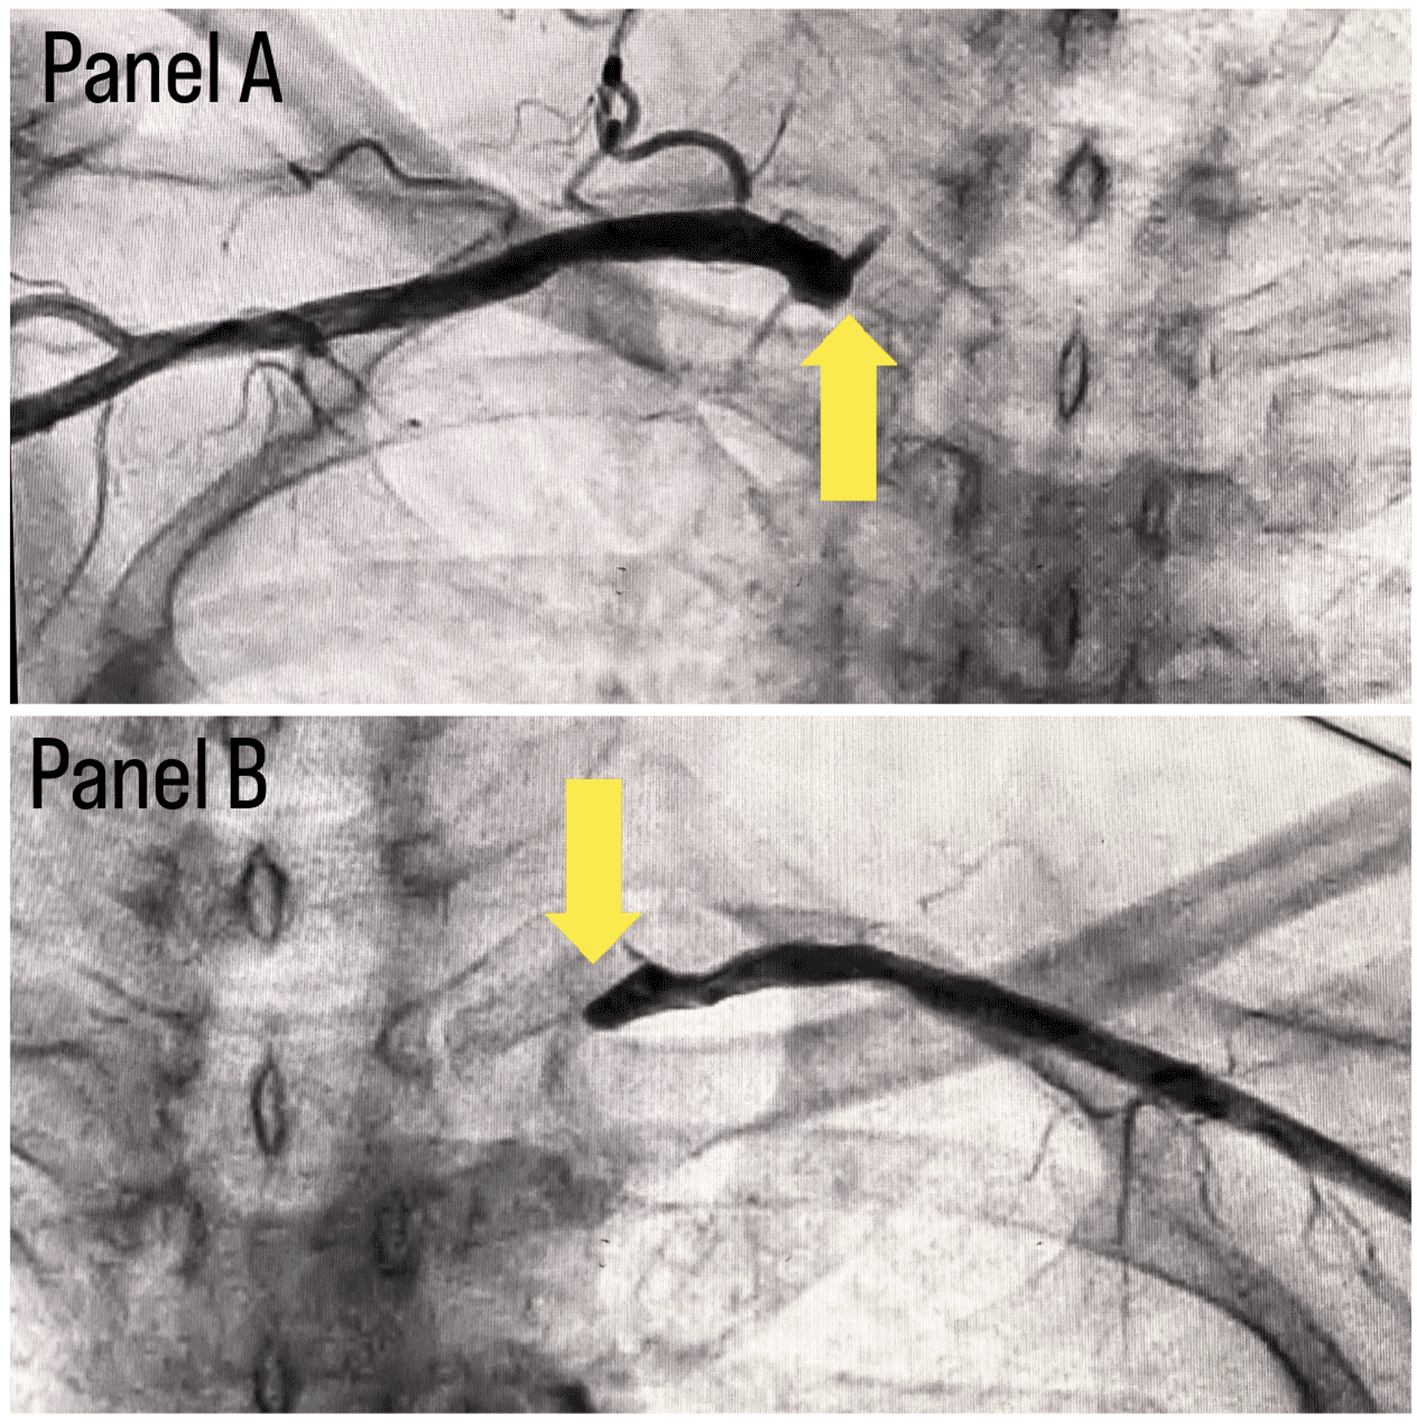

Coronary angiography was done and a triple vessel coronary artery disease was diagnosed as shown in Figure 1; in which, panel A shows stenosis in proximal Left circumflex artery (LCX) with a black arrow, panel B shows a stenotic lesion in proximal Left anterior descending artery (LAD) with a black arrow and panel C shows 100% stenosed Right coronary artery (RCA) with a black arrow. A subclavian puncture was taken to look for a subclavian artery considering the claudication symptoms of the patient and peripheral vascular disease was diagnosed with bilateral subclavian artery stenosis as shown in Figure 2, in which panel A shows right subclavian artery stenosis and panel B shows left subclavian artery stenosis marked with yellow arrows. Considering the severity of claudication pain in our case, bilateral renal and femoral arteries were also checked via aortic flush and bilateral renal artery ostial stenosis was seen. Figure 3 panel A shows right renal ostial stenosis and panel B shows left renal ostial stenosis marked with red arrows.